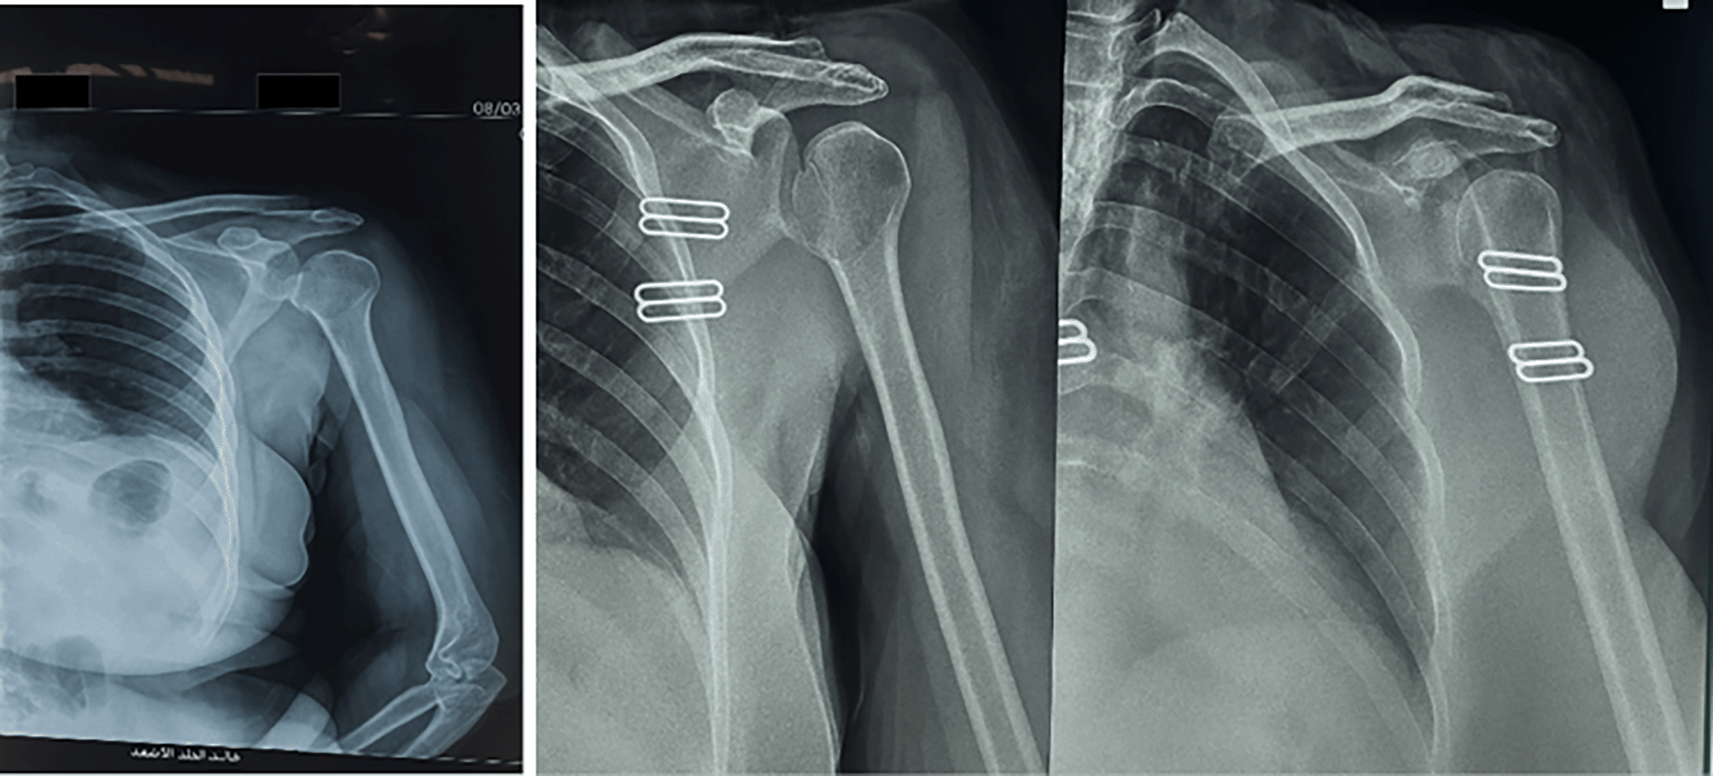

A 52 years old female patient presented to a private clinic in Fallujah city on 8/3/2025, with left shoulder pain and limitation of movement for 3 months. Her symptoms occurred after an episode of convulsions.

On examination, there was loss of external rotation movement of the shoulder. The X-rays showed a light-bulb appearance ( Figure 5). The CT scan: shows Reverse Hillsach lesion ( Figure 6).

The management plan involved surgical reduction of this dislocation using the Modified McLaughlin procedure. The patient was admitted to the operative room at Fallujah Teaching Hospital to undergo the surgical procedure using the deltopectoral approach to reduce the dislocation by the open method with transfer of the subscapularis with its lesser tuberosity to the defect (Reverse Hillsach) on the anterior part of the Humeral Head with Bone Graft ( Figure 7).

Postoperatively, the patient wore a Gunslinger sling for one month followed by exercise. The postoperative radiograph is shown in ( Figure 8).